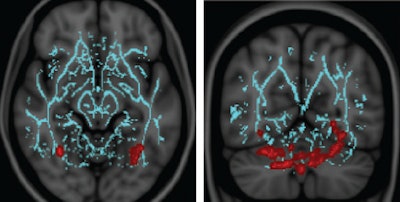

The condition is called vestibulopathy. Patients with mild traumatic brain injury (TBI) and vestibular symptoms had lower fractional anisotropy values in the cerebellum and fusiform gyri than control subjects with no symptoms, wrote a team led by Dr. Lea Alhilali, an assistant professor of radiology at the University of Pittsburgh Medical Center (UPMC).

The group used fractional anisotropy values from DTI-MRI to measure damage to the brain's signal-transmitting white matter. The lower the fractional anisotropy, the greater the damage to the tissue.

When they examined the DTI-MRI results, the researchers found that patients with mild TBI and vestibular symptoms had decreased fractional anisotropy values in brain regions not previously suspected to be involved in post-traumatic vestibulopathy.

"Interestingly, the reason that the symptoms were different between concussion patients with and without vestibulopathy was in the cerebellum, which is the part of the brain that is vital for balance," Alhilali said. "Also it was in the fusiform gyrus."

A region of the brain that integrates vision between the left and right eyes to create a 3D visual field is in the fusiform gyrus. "So both of these regions help to explain why these patients are having the symptoms," she added.